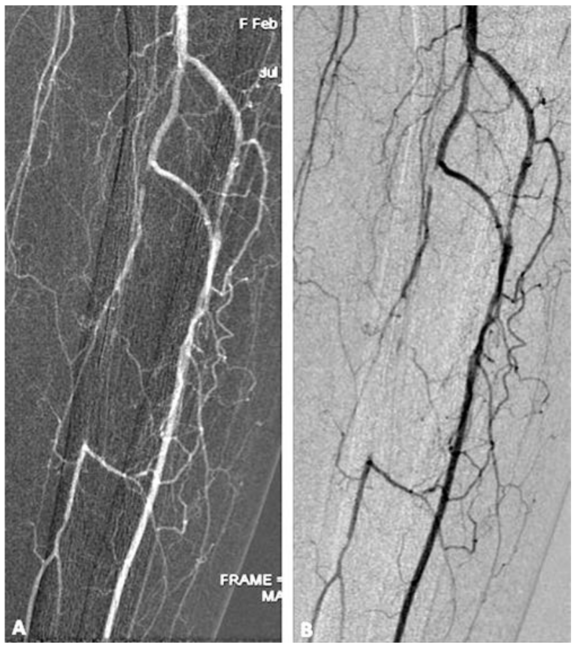

As a final point, the use of CO2 as an intraarterial contrast agent also required the use of digital subtraction technology. This technology detects a very low concentration of contrast agent by subtracting the presence of soft tissue before contrast injection and enhancing the postcontrast images through manipulation and amplification of a digitized radiographic image. Current angiography procedures are now set up with CO2 postprocessing “stacking” software. CO2 produces contrast by causing complete displacement of the blood column in the vessel. In each x-ray acquisition, the CO2 will sometimes fail to opacify the entire field during the same run. For postprocessing visualization of the entire vasculature, “stacking” techniques are used to stack the individual images on top of each other to form a single composite image.9 The ability to stack these images is essential for obtaining a final picture that delineates the true anatomy. By employing some of the strategies previously mentioned, excellent imaging of the lower extremities can be obtained (Figures 1, 2, and 3).